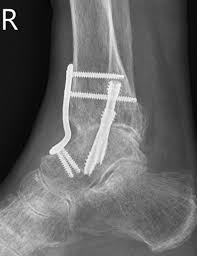

Fijación del Tobillo: Artrodesis

La artrodesis de tobillo continua siendo la mejor opción para el tratamiento de la artrosis de tobillo avanzada que no responde al tratamiento conservador. Es especialmente útil en pacientes jóvenes, con mucha vida por delante en los que la implantación de una prótesis no sea recomendable o en aquellas personas con enfermedades que puedan comprometer la implantación de la prótesis.

Esta cirugía consiste en fusionar la articulación del tobillo dejándola fija pero sin dolor. Aunque el resultado de esta técnica pueda parecer muy limitante, los pacientes pueden caminar sin dolor tras la recuperación, aunque habrá que emplear calzado tipo balancín u otro tipo de ortesis para caminar de una forma más ergonómica.

Lo ideal es realizar la cirugía antes de que aparezcan deformidades, con el objetivo de evitar la necesidad de realizar procedimientos más complejos sobre el pie. Como hemos comentado, la artrodesis obtiene un alivio importante del dolor, aunque se pierde la flexoextensión del tobillo.